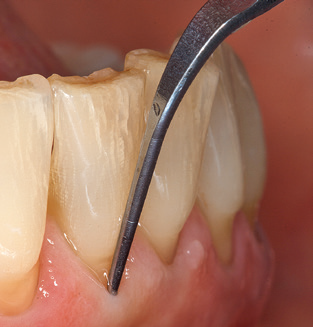

Fig. 4: Flexible probes with millimetre markings are recommended for the probing of dental implants (e.g. Colorvue Kit PCV11KIT6, Hu­Friedy). – Fig. 5a and b: A straight working tip (1P, W&H Dentalwerk Bürmoos GmbH) is a suitable instrument for use on all natural teeth. – Fig. 6: Curved working tips (3Pr/3Pl, W&H Dentalwerk Bürmoos GmbH) lend themselves to the processing of difficult-to-reach areas of the tooth and root surfaces (e.g. furcations). – Fig. 7: The tapered, hexagonal implant cleaning tip (1I, W&H Dentalwerk Bürmoos GmbH) permits atraumatic and efficient cleaning of the crown and abutment surfaces. – Fig. 8: Titanium and carbon curettes are suitable instruments for the manual cleaning of the implant surfaces.

Following machine cleaning of the tooth and implant surfaces, the surfaces of the natural teeth are cleaned manually using standard hand instruments. When performing manual cleaning, particular attention must be given to maintaining the correct angle of application, appropriate sharpness, good support and working with the curette from apical to coronal. Either titanium or carbon curettes should be used for post-cleaning of the implant structures (Fig. 8). In addition to the use of ultrasonic devices, power jet devices can also be used in conservative dentistry. However, it must be taken into consideration that these procedures are not suitable for removing hard deposits and thus they cannot replace the use of hand instruments and ultrasonic instruments completely. In all cases, cleaning is followed by mechanical polishing of the accessible tooth and implant surfaces with polishing cups and polishing compounds (Fig. 9).

An array of special carbon, titanium and plastic curettes and scalers are available for the mechanical cleaning of implant surfaces by hand.(13-15) Overall, the efficacy of the biofilm removal with the available hand instruments is predominantly assessed as ineffective.(11) Whilst plastic curettes in particular have only a minimal detrimental effect on the implant surface and afford patients a high degree of comfort, their poor efficiency with regard to biofilm removal and their incapacity to remove calculus and subgingival concretions contraindicate their use.(16,17) Today, the use of carbon and titanium curettes is viewed as being more efficient, with the result that, if at all, these can be recommended for use as hand instruments.(11)